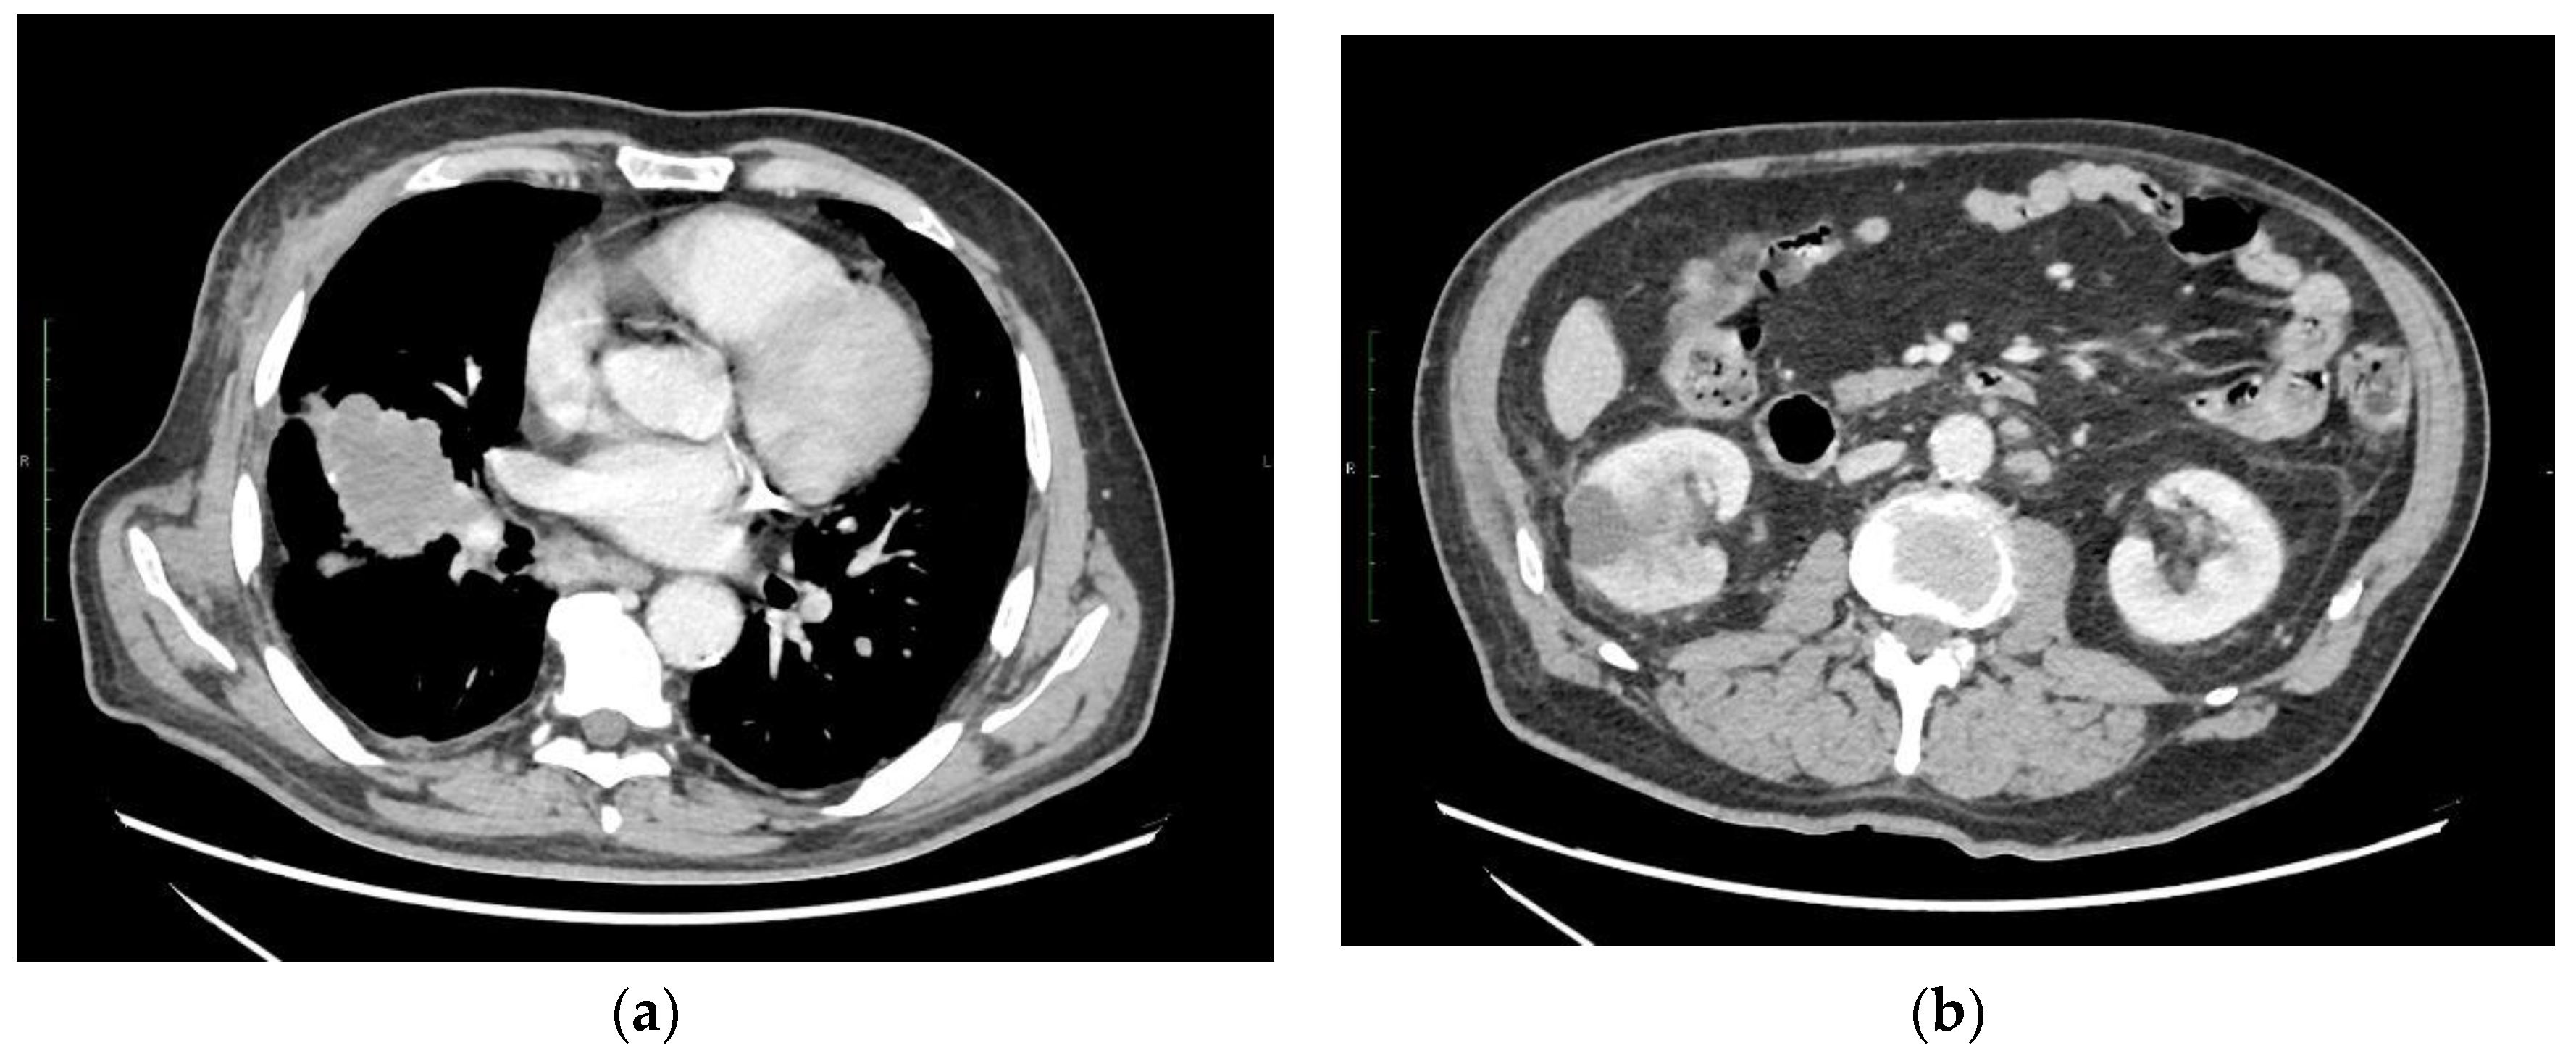

2. Case Description